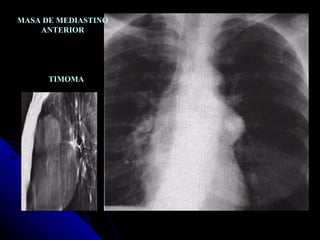

MASA DE MEDIASTINO ANTERIOR TIMOMA

MASA DE MEDIASTINOANTERIOR TIMOMA